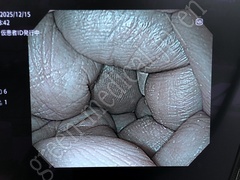

Video System Center EVIS X1 CV-1500

Fabricante

OLYMPUS

Tipo

EVIS X1 CV-1500

Inventario

115707